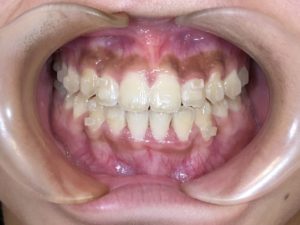

🦷現在2年目

トレーニングをとっても頑張って頂き、開咬が改善されました💯

途中思うよう進まず辛い時期もあったかと思いますが、

諦めずにトレーニングに協力して頂きました😭

あとは微調整をして終了となりますが、油断は禁物です!

保定期間も乗り越えて綺麗な歯並びを保ってほしいですね☝🏻